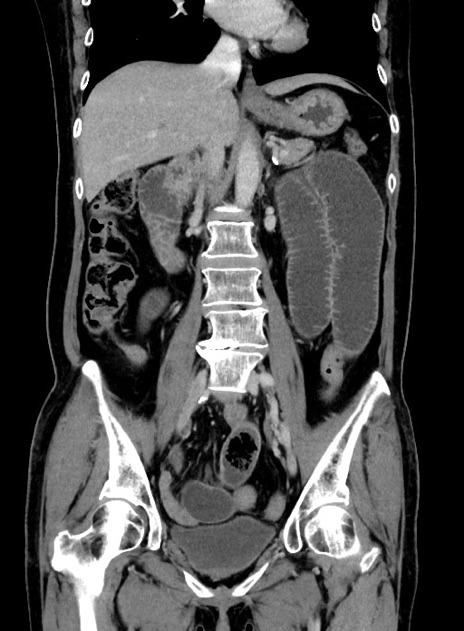

症例9(冠状断像)

【症例】 60歳代女性

【主訴】むかつき、みぞおちの痛み

【現病歴】3日前よりむかつきがあり、食事がとれない。

【既往歴】糖尿病

【身体所見】発熱なし、心窩部圧痛軽度あるも、腹膜刺激症状なし。

【データ】WBC 7400、CRP 1.92